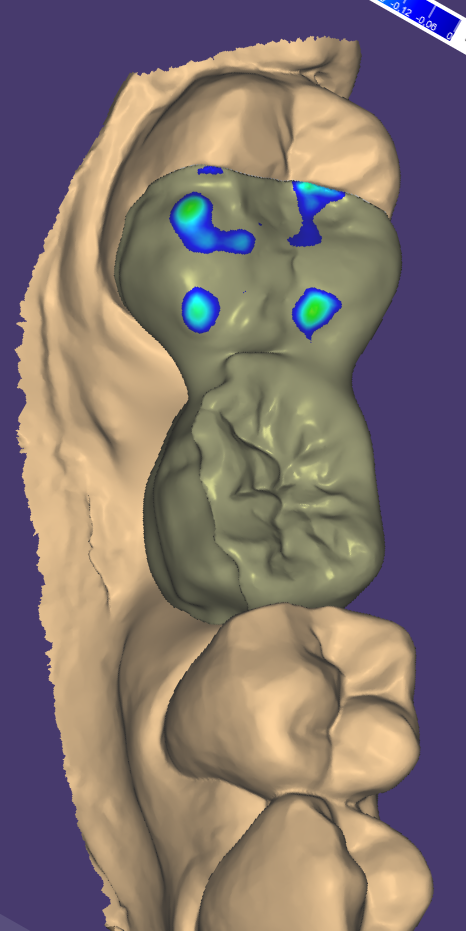

Relativement récents, les bridges collés cantilever postérieurs constituent une alternative fixe, fiable et véritablement minimalement invasive aux implants dans les secteurs postérieurs. Cette thérapeutique qui repose sur des indications bien précises est parfois débattue avec passion sur les réseaux sociaux ou dans les congrès scientifiques. Cependant des études cliniques existent, tout comme des recommandations validées dans des journaux internationaux. Leur succès repose sur des préparations et des principes biomécaniques rigoureux, pourtant simples à intégrer au quotidien. Cette intervention propose un guide clair et opérationnel incluant indications, étapes clés, protocoles d’adhésion et réglages occlusaux pour les mettre en œuvre avec confiance et reproductibilité.